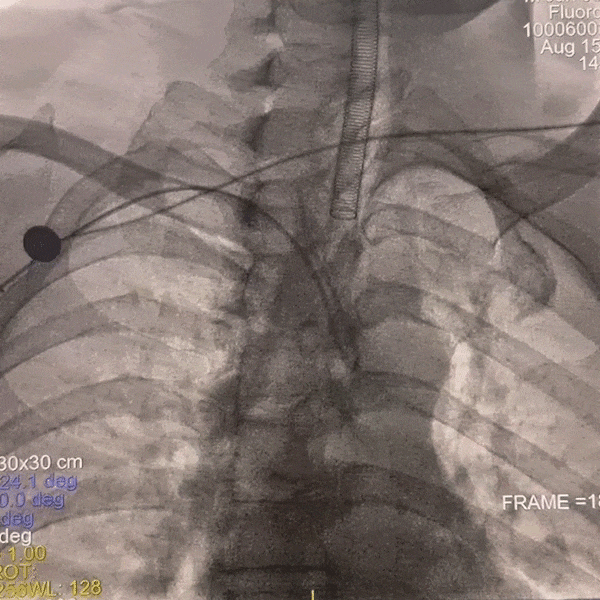

通路建立:患者主动脉弓造影显示Ⅲ型弓,病变为右侧大脑中动脉栓塞,故选择赛诺神畅APEX TRA GC™5F-130 SIM2导引导管同轴长鞘建立通路。

动脉长鞘怎么置入一技之“长”丨经桡及经股困难入路应用赛诺神畅APEX TRA GC™导引导管建立通路病例合集_https://www.jmylbn.com_新闻资讯_第7张

Ⅲ型弓

动脉长鞘怎么置入一技之“长”丨经桡及经股困难入路应用赛诺神畅APEX TRA GC™导引导管建立通路病例合集_https://www.jmylbn.com_新闻资讯_第8张

长SIM2导管成袢

动脉长鞘怎么置入一技之“长”丨经桡及经股困难入路应用赛诺神畅APEX TRA GC™导引导管建立通路病例合集_https://www.jmylbn.com_新闻资讯_第9张

顺利超选入无名动脉

跟进长鞘至右侧颈内动脉,输送068抽吸导管,释放6*30mm 取栓支架。